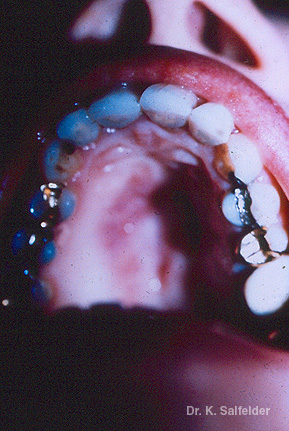

Abb. 13,4: Phaeohyphomykose

Die Veraenderungen in der Mundschleimhaut waren durch Alternaria alternata verursacht